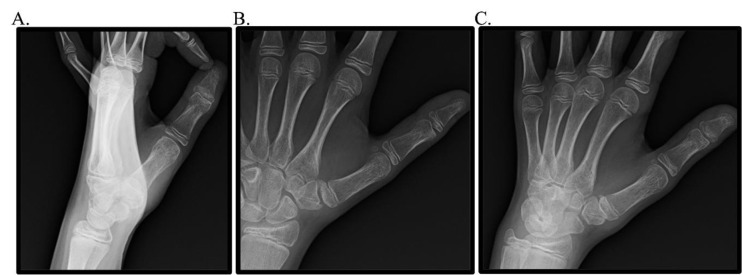

小儿班尼特等效型骨折是一种罕见但又重要的发病率和诊断复杂性的来源。尽管儿科患者具有显著的重塑潜力和弹性,但如果处理不当,这些损伤会带来多种后遗症,如残余畸形、疼痛、功能限制和前瞻性加速关节病。鉴于文献的缺乏和前瞻性、严格的试验的缺乏,这些损伤的最佳管理仍然存在争议。本研究展示了作者对两例儿童班尼特等效骨折的经验,一例保守治疗,一例手术治疗,强调了提供者在识别和治疗这些损伤时保持警惕和注意力的必要性。

Pediatric Bennett-equivalent type fractures represent an uncommon yet consequential source of morbidity and diagnostic complexity. Despite the remarkable remodeling potential and resiliency of the pediatric patient population, if managed inappropriately, these injuries are associated with multiple sequelae such as residual deformity, pain, functional limitations, and prospective accelerated arthrosis. Given the paucity of literature and absence of prospective, rigorous trials, the optimal management of these injuries remains contentious. The present study exhibits the authors' experience with two pediatric Bennett-equivalent fractures, one managed conservatively and one operatively, highlighting the necessity for provider vigilance and attentiveness in recognizing and treating these injuries.